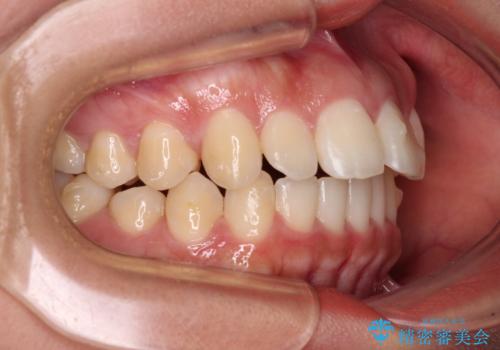

飛び出した上顎前歯 インビザラインで引っ込める

- 前歯の突出感を気にして来院された患者様です。

奥歯の咬み合わせは理想的な咬合に近く、インビザラインでも十分に対応できる歯列でした。

舌の突出癖を改善するためのトレーニングを行いつつ、上下歯列全体を後方に移動させ、更にはIPR(歯と歯の間を削る)によりスペースを獲得することで、口元の突出感を改善することとしました。